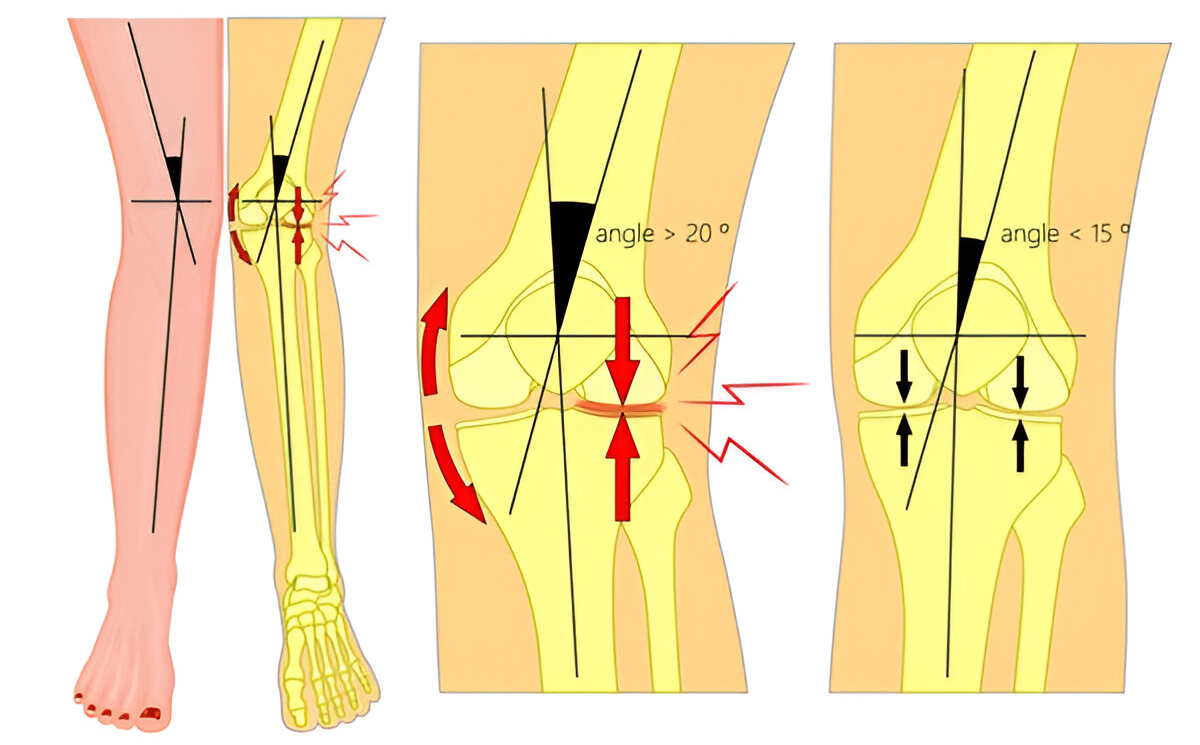

Desde el punto de vista anatómico, el genu valgo representa una alteración en el eje de carga entre el fémur y la tibia, generando una distribución anómala de las fuerzas sobre la articulación de la rodilla. Esta desalineación puede provocar sobrecarga en la zona externa (compartimento lateral) de la rodilla, contribuyendo con el tiempo a lesiones de cartílago, dolor y, en casos avanzados, artrosis.

Una vez realizada la evaluación clínica, el siguiente paso es obtener imágenes detalladas de las rodillas y las piernas para observar con precisión la alineación ósea. Las radiografías son la herramienta más comúnmente utilizada para este fin y permiten medir el ángulo de alineación de las rodillas. El ángulo varía dependiendo de la gravedad del genu valgo, y se puede calcular midiendo la distancia entre las líneas que forman los ejes del fémur y la tibia. Este ángulo se conoce como el ángulo de la deformidad en «X».

Las radiografías permiten clasificar la severidad del genu valgo y proporcionan detalles cruciales sobre la relación entre la tibia y el fémur, que ayuda a planificar el tratamiento adecuado. También se pueden identificar otras condiciones asociadas, como lesiones en los huesos o cartílago, o patologías articulares como la osteoartritis, que podrían estar contribuyendo a la deformidad.